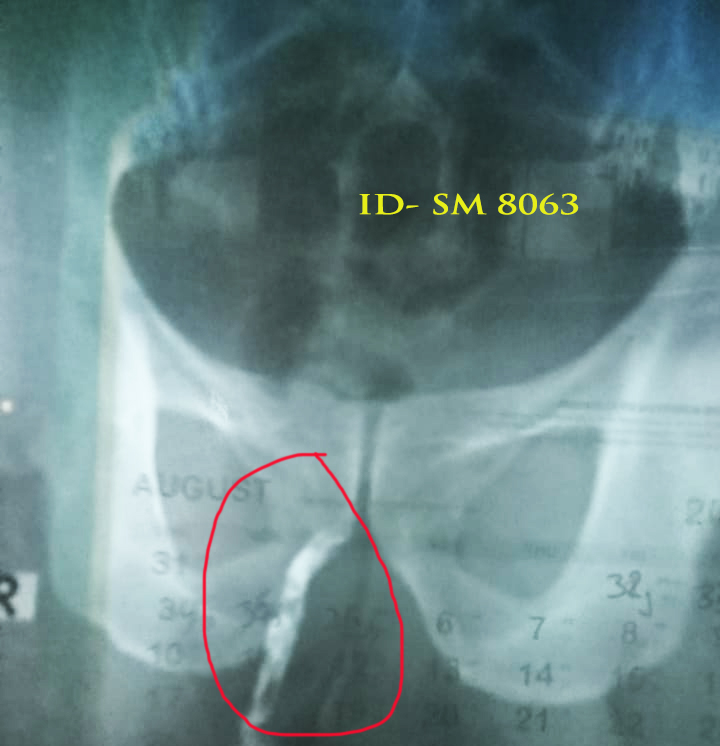

Anal Abscess (মলদ্বারের ফোঁড়া): - মলদ্বারের চারপাশে পুঁজ জমে ফোঁড়া তৈরি হওয়া। - সংক্রমণ বা গ্রন্থির প্রদাহ এর কারণ। - লক্ষণ: ১. ব্যথা ও ফোলা। ২. পুঁজ নির্গমন। ৩. জ্বর ও দুর্বলতা।

জটিলতা: - দীর্ঘস্থায়ী Anal Fissure → Chronic Fissure। - Anal Abscess → Fistula তে রূপ নিতে পারে। - অতিরিক্ত রক্তপাত, ব্যথা ও মানসিক অস্থিরতা।